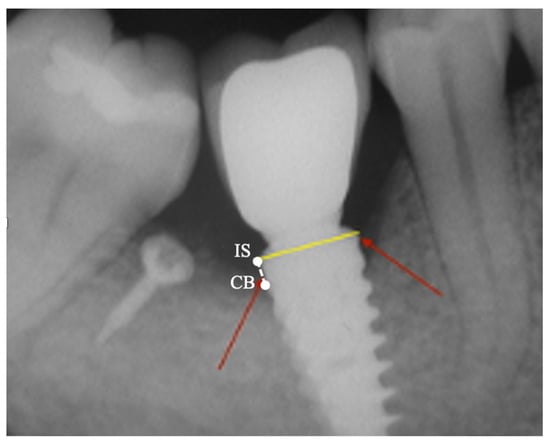

2.3. Peri-Implant Bone Levels Assessment

| Variable (mm) | Mean | Std dev | Std Err | 95% CI |

|---|---|---|---|---|

| MBLm | 0.11 | 0.49 | 0.16 | −0.46/0.24 |

| MBLd | 0.03 | 0.19 | 0.06 | −0.17/0.11 |